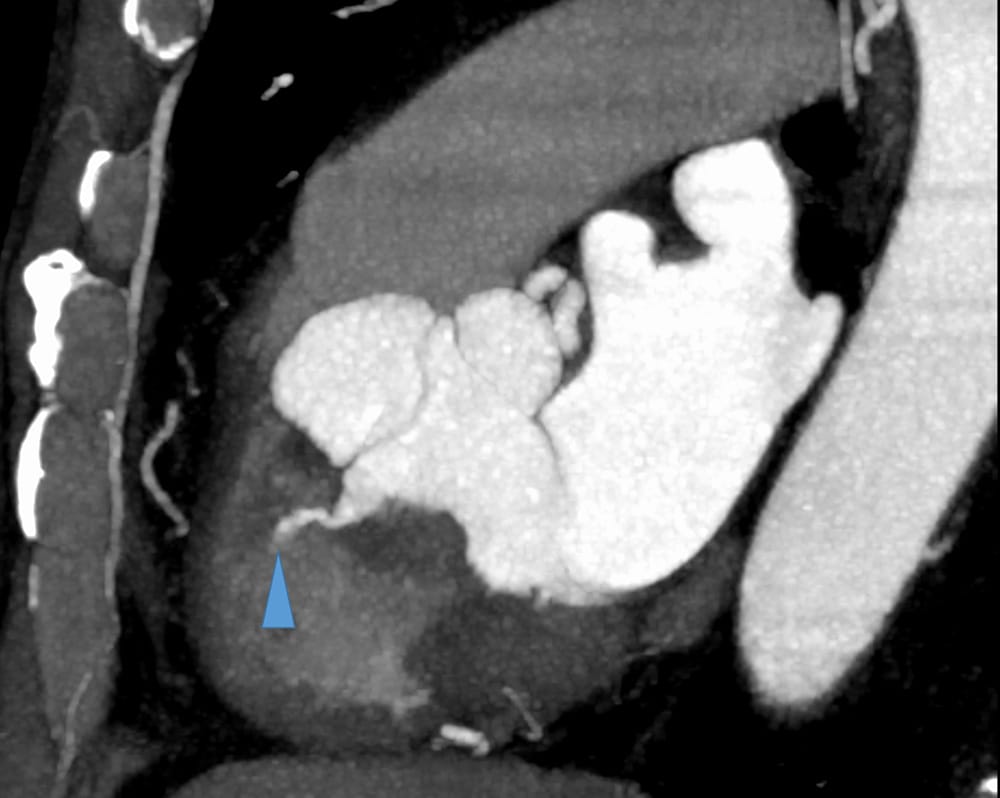

図4.心臓CT MIP MPR画像(収縮末期)

シャント量は少ないがMPR画像上も造影剤のjetが見られる(矢頭)。